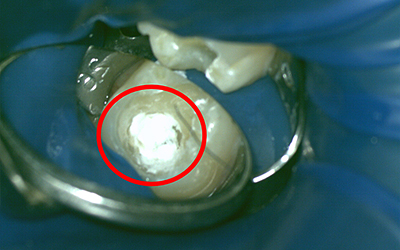

マイクロスコープで直接神経の状態を確認することです。

ポルトランドセメントを主成分とする薬で、このセメントを使う事により本来なら神経を取らざる得ない場合でも神経の保存が可能になりました。

| 注意事項 | MTAによる生活歯髄療法の適用と診断したが、すべての症例で歯髄保存が必ずしも成功出来るわけではありません |